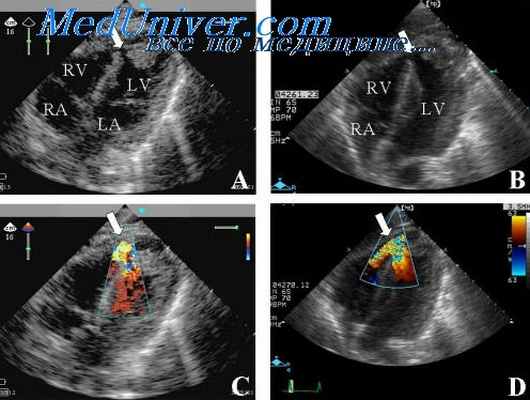

Цветовой допплер (Color Doppler). Цветовой допплер - аналог импульсного допплера, где направление и скорость кровотока картируется различным цветом. Так кровоток к датчику принято картировать красным цветом, от датчика - синим цветом. Турбулентный кровоток картируется сине-зелено-желтым цветом.

Тканевый допплер (Tissue Velocity Imaging). Принцип данного метода основан на картировании направления движения тканей определенным цветом. Таким образом красным цветом обозначают движение к датчику, синим - от датчика. Изучая направления движения стенок левого и правого желудочков в систолу и диастолу с помощью TVI можно обнаружить скрытые зоны нарушения локальной сократимости. Совмещение двухмерного исследования в режиме TVI с M-модальным увеличивает точность диагностики.